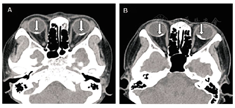

既往5年前头部受过拳击伤,否认全身疾病史及家族史。眼科检查:视力右0.3,矫正无提高,左0.07,矫正无提高;眼压:右19.0 mmHg,左17.8 mmHg。双眼前节正常,散瞳见双眼低,如图1A、图1B。眼部B超检查如图2A、图2B。眼眶CT扫描:双侧眼球后壁见对称性高密度弧形钙化影(箭头所指),较长者直径0.7 cm,最高CT值468 Hu(图3A)。荧光素眼底血管造影(fundus fluorescein angiography,FFA)图4。结合眼底相、B超、眼眶CT及FFA检查,诊断:双眼脉络膜骨瘤。

病例2:患者女,48岁,自述右眼视物不清7年余,左眼10天余,于2016年5月26日来我院就诊。既往8年前头部受过雷击伤,否认全身疾病史及家族史。眼科检查:视力右0.15,-1.00 DC×15→0.25,左数指/30 cm,矫正无提高。双眼前节正常,散瞳见双眼底如图1C、图1D。眼部B超检查如图2C、图2D。眼眶CT扫描:双侧眼环后份及周围局部眼球可见条状高密度钙化影(箭头所指),最高CT值572 Hu(图3B)。双眼FFA如图5,诊断:双眼脉络膜骨瘤。

B超的典型声像特征为近乳头附近可见条形强回声斑,其后方声影明显,降低增益值此强回声斑仍存在,而球壁等正常组织的回声减弱甚至消失[7],但肿瘤回声仍存在。脉络膜骨瘤特征性的CT表现为眼球后极部眼环上呈现弧形或半环状光滑锐利的致密影[8],脉络膜骨瘤行FFA检查早期即有强荧光点出现,强荧光代表肿瘤内异常脉络膜血管,晚期时不规则弥漫斑点状强荧光持续存在[9]。本文2例患者改变与上述相符合。

脉络膜骨瘤可依据眼底表现、B超、眼眶CT及FFA表现做出正确诊断,B超及眼眶CT典型表现具有诊断意义。脉络膜骨瘤是脉络膜占位性病变,呈良性,应与脉络膜黑色素瘤、脉络膜转移癌、脉络膜血管瘤相鉴别,认识本病的临床特点及各种辅助检查特征,可避免误诊为眼内其他肿瘤[10]。